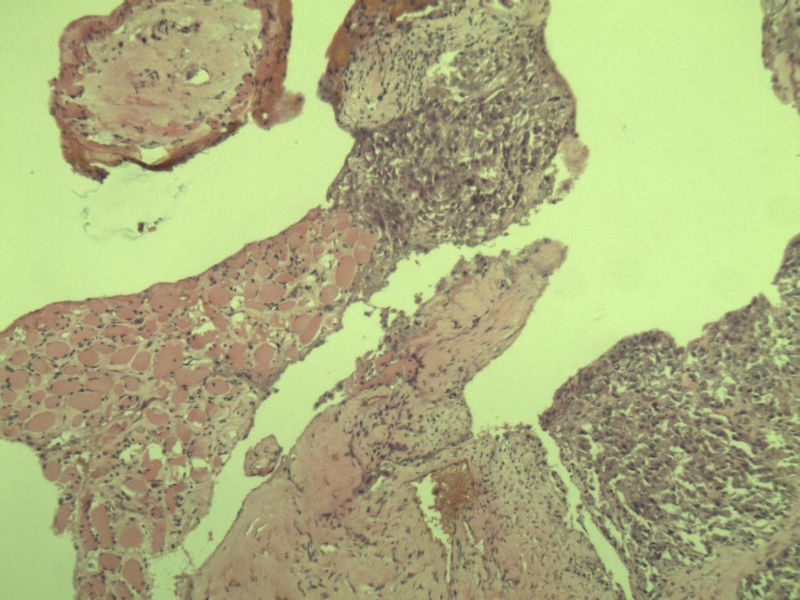

女 70岁 右颈部 头皮 多发皮下结节      取颈部部分结节送检 灰白小组织 1 块,直径 0.4 cm。 请问这个是什么?

肿瘤细胞大,上皮样,核空泡状,核仁明显,胞质嗜酸性或透明。

考虑:恶性黑色素瘤?

近心型上皮样肉瘤?

软组织透明细胞肉瘤?

上皮样多形性脂肪肉瘤?

等免疫组化标记!

此片染色欠佳,取材或切面也有问题,加大了诊断的难度,恶黑确实需要考虑,但其他一些转移癌也需要排除,比如肺癌之类的,还是期待免疫组化!